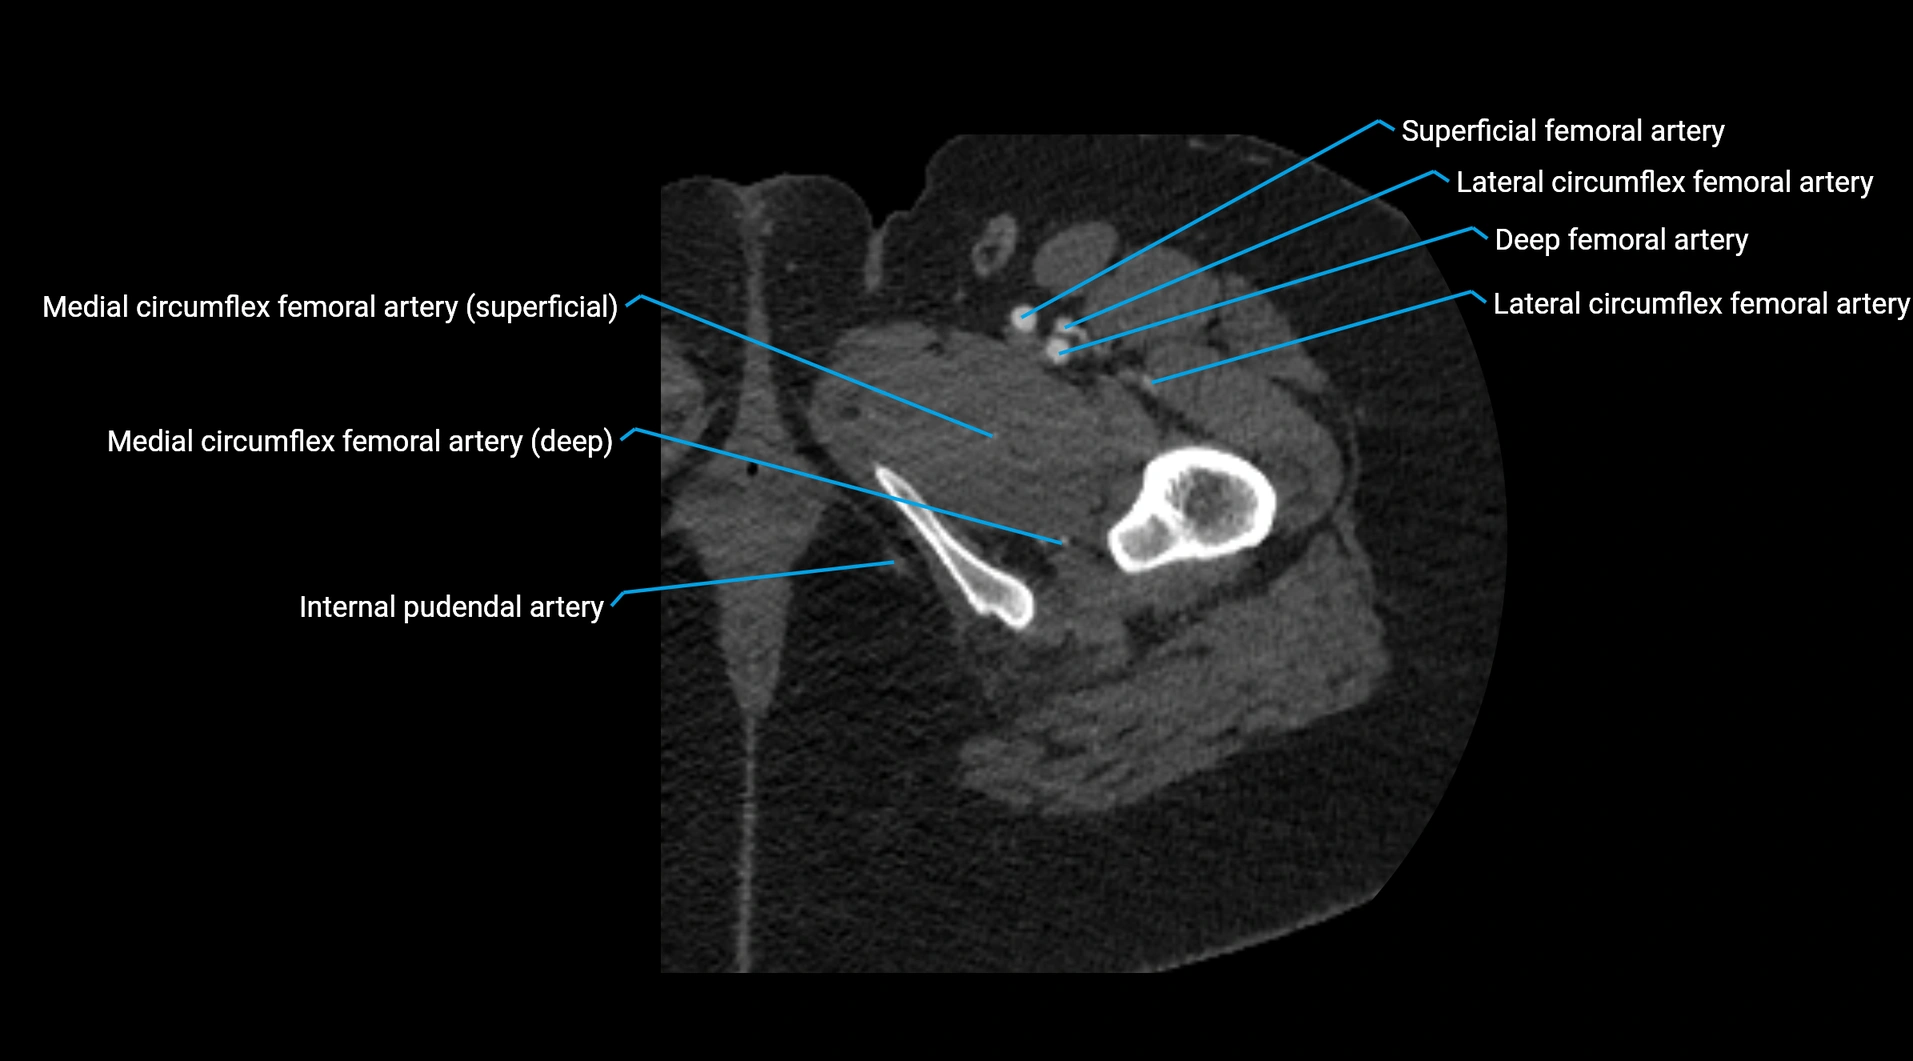

CT Appearance

Non-contrast CT:

• Appears as a tubular soft tissue structure anterior to vertebral bodies

• Calcified atherosclerotic plaques appear as hyperdense foci along the wall

• Useful for screening abdominal aortic aneurysm (AAA) size and mural calcification

Contrast-enhanced CT (CTA):

• Gold standard for abdominal aortic imaging

• Provides excellent detail of lumen, wall, aneurysm, thrombus, and branch vessels

• Multiplanar and 3D reconstructions help in aneurysm measurement, stent graft planning, and dissection evaluation

• Detects acute rupture, traumatic injury, or occlusion with high sensitivity

CT images

image